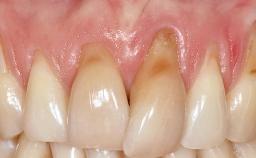

Periodontal Plastic Surgery and Prosthetic Procedures to Treat Peri-Implant Soft-Tissue Dehiscences

A 30-year-old woman was referred by her general dentist for evaluation of an esthetic complication related to previous implant treatment for congenitally missing maxillary lateral incisors. The patient’s chief complaint was the inadequate esthetic appearance of her smile. The case demonstrates the use of a combined approach to achieve optimal results. Two different flap designs - a tunnel technique and a coronally advanced flap - are employed based on the surgical objectives for the affected site.